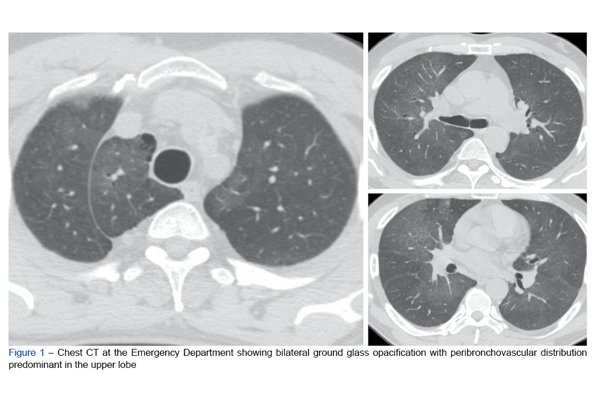

A pneumonite associada a impermeabilizantes com fluoropolímeros é uma entidade com poucos casos relatados e que pode resultar duma exposiçã...